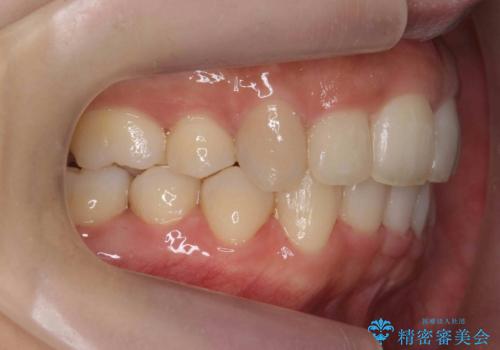

①上下左右合計4本抜歯(口元は一番下がるプラン、上の奥歯をさらに後ろに下げる必要があるため②より時間がかかる、上下正中は合う)

②上の歯を2本抜歯、下の歯は前歯1本と最小限の抜歯(矯正治療は早く終わる、口元は下がる、抜歯は3本、上下の正中は合わない)

を提示し、

②を選択されました。

下顎がとても小さく後方位であるため、オトガイの閉口時のシワは完全になくすことは難しかったですが、前歯も大きく下がり満足していただきました。